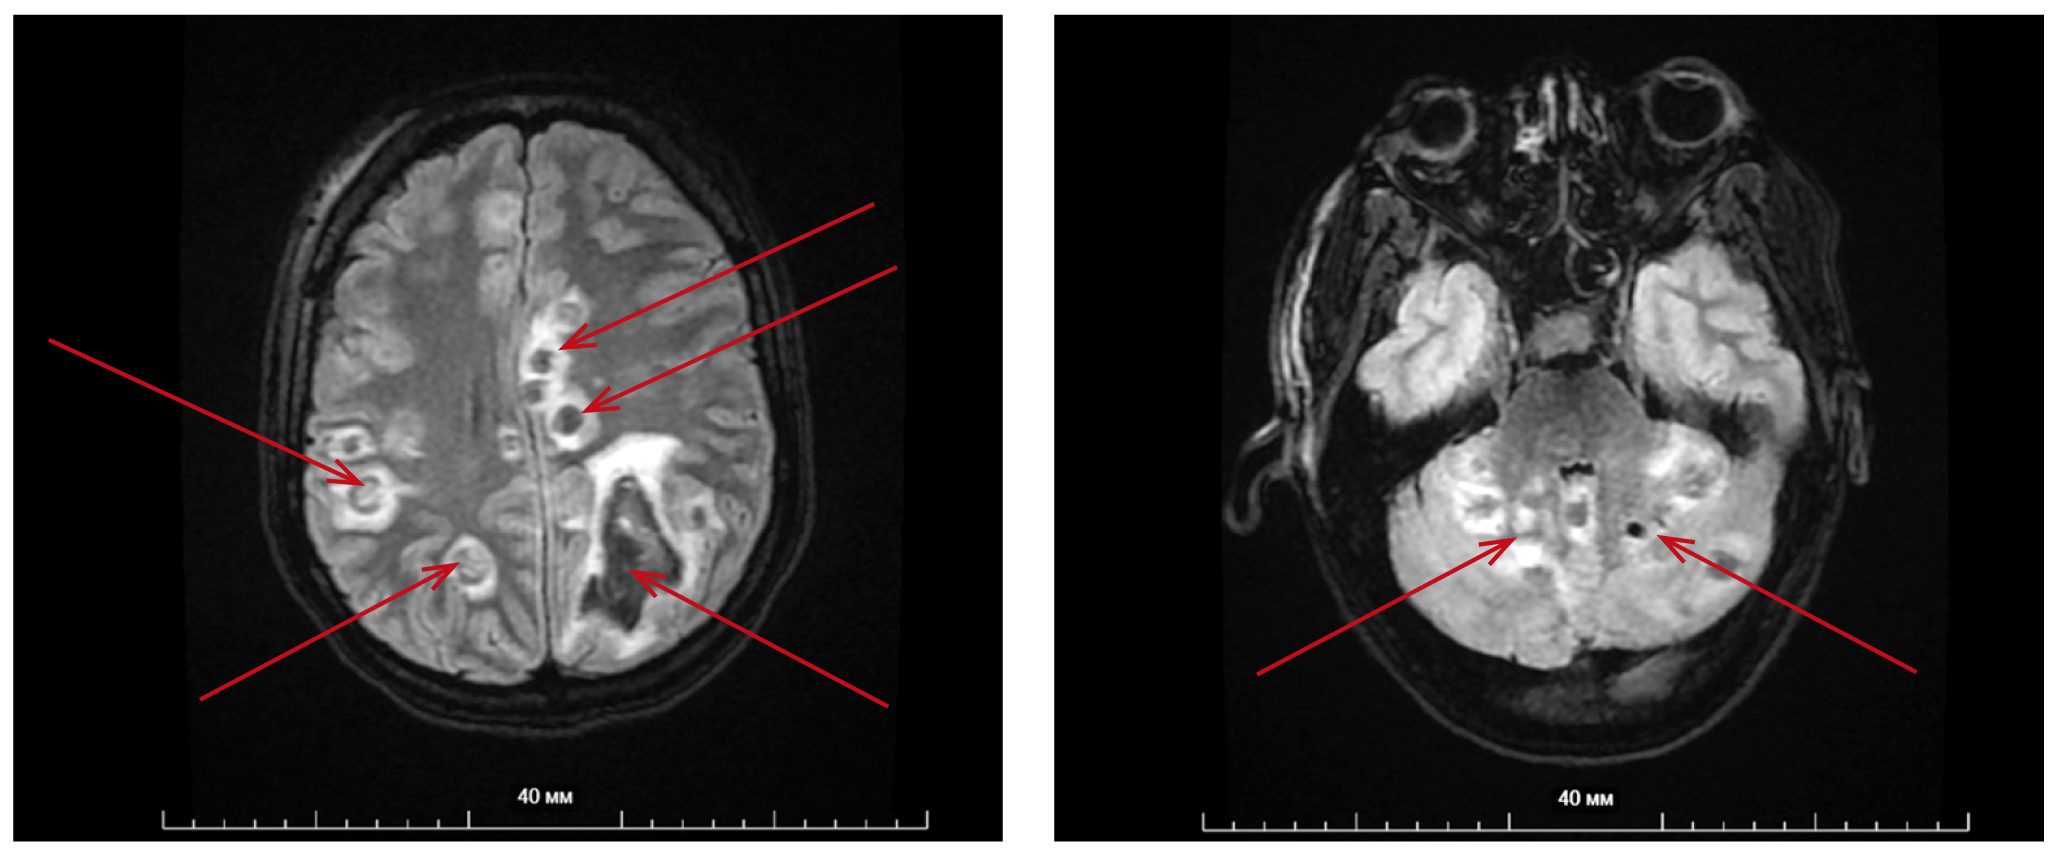

С диагнозом «Геморрагический инсульт в левой гемисфере, правосторонний гемипарез» пациентка госпитализирована в отделение нейрореанимации. В последующем была проведена магнитно-резонансная томография головного мозга (рис. 2): выявлены признаки мультифокального поражения головного мозга; внутримозговое кровоизлияние (метастазы с кровоизлияниями? нейроинфекция?).

Рис. 2. Тот же пациент. Магнитно-резонансная томография головного мозга: мультифокальное поражение головного мозга, внутримозговое кровоизлияние. / Fig. 2. The same patient. Magnetic resonance imaging of the brain: multifocal brain damage, intracerebral hemorrhage.